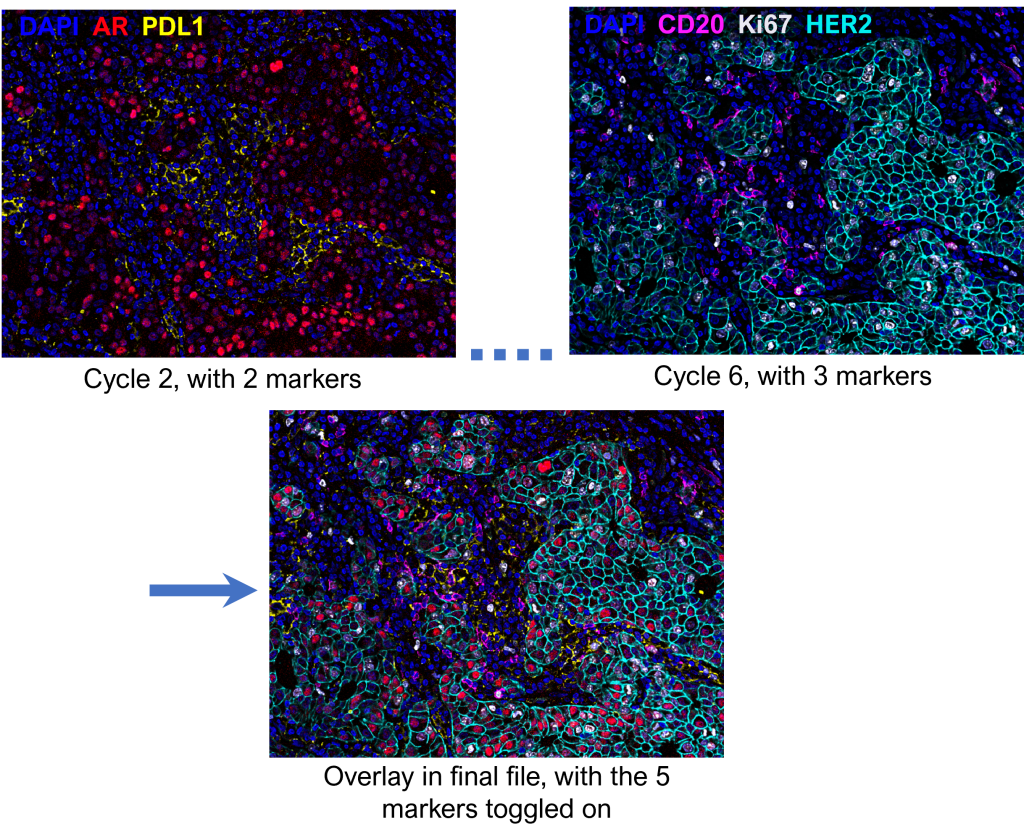

Akoya Biosciences provides processing software which manipulates the original images into a final file that contains all markers, with DAPI labeling the DNA of nucleated cells. The following are some noteworthy steps during processing:

The processing software should be able to accommodate ROI’s up to 10 x 8 mm in size. Please consult us if large ROI’s are necessary for your project.The stitched images from each Cycle are overlaid to be part of one final file, in which marker visualization can be turned on and off.

Example: